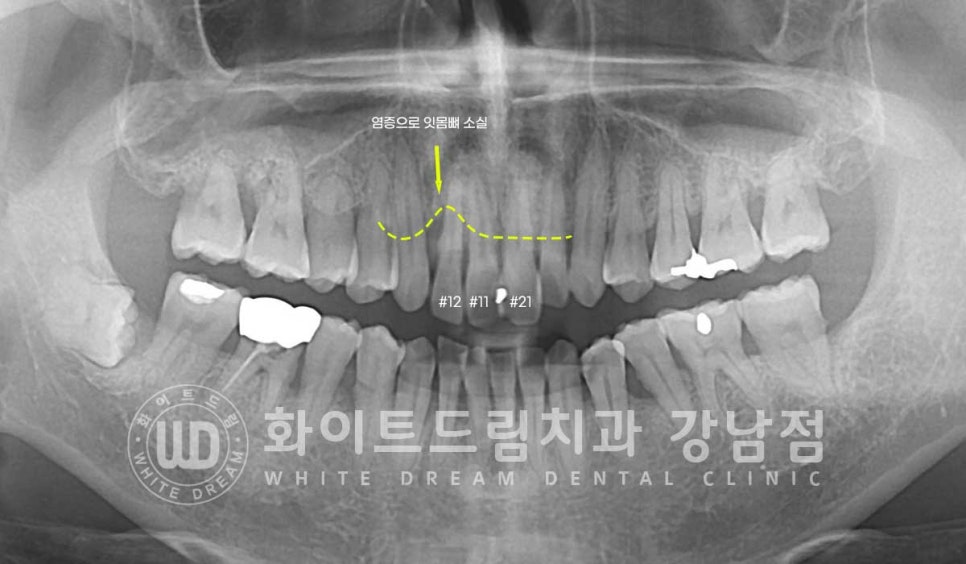

환자분이 증상을 호소하시는 치아는

앞니 3개 (12, 11, 21번 치아)입니다.

육안으로 보기엔 11번, 21번 치아 사이 큰 충치가 발생해있고

11번 치아가 전체적으로 어둡게 변색된 것이 확인됩니다.

그리고 동요도 검사 시 12번 치아가 심하게 흔들림을 호소하고 있었는데

치아의 상태를 보다 정확하게 확인하기 위해 치근단 사진을 촬영해 봤습니다.

12번 치아의 치주 인대가 손상되어 염증이 발생했고

이로 인해 주위 잇몸뼈가 녹기 시작한 것으로 추측되었습니다.

또한 11번 변색된 치아 끝 부위에 치아 뿌리 염증이 자리를 잡고 있는 것이 확인됩니다.

아마 외상을 당하셨을 때 치수가 손상되었고 천천히 괴사가 일어나

치아 뿌리에 염증이 발생한 것으로 추측되었습니다.

이 치아 뿌리 염증과 인접면 충치 치료를 진행하기 위해

11번, 21번 치아는 신경치료를 진행하기로 하였고

잇몸뼈가 심하게 녹아 흔들림이 심한 12번 치아는 발치 후 임플란트를 식립하기로

환자분과 상의 후 결정되었습니다.